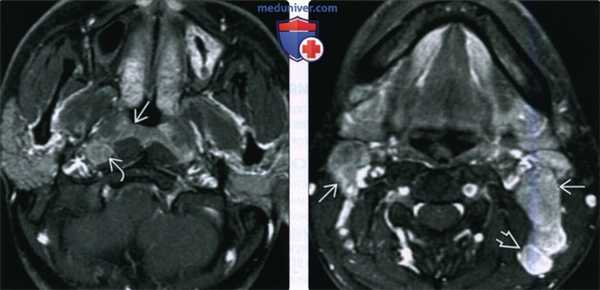

(Слева) При МРТ Т1 C+FS в аксиальной проекции, выполненной мужчине 26 лет из Азии с объемными образованиями шеи, определяется минимально асимметричный мягкотканный компонент в слизистой оболочке носоглотки, признаков инфильтрации превертебральных мышц не выявлено. Отчетливо визуализируется увеличенный заглоточный лимфоузел.

(Справа) При МРТ Т1 С+ FS в аксиальной проекции у этого же пациента визуализируются увеличенные лимфоузлы второго и пятого уровня, в которых были обнаружены метастазы недифференцированного некератинизирующего рака (третья стадия, T1N2), сочетанного с вирусной инфекцией Эпштейна-Барр.